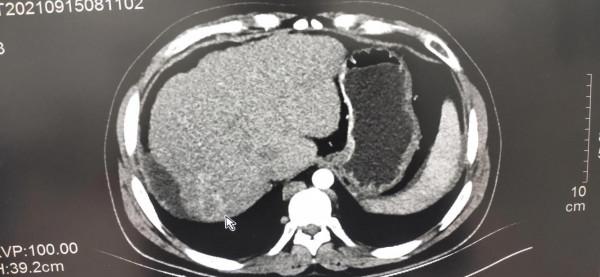

前幾天遇到一位32歲的年輕男性患者,以腹痛、腹脹就診。門診上腹部CT檢查發現嚴重的肝硬化,並且肝右葉可見片狀低密度病變,臨近肝臟邊緣凹陷並有少量腹水。當時考慮可能又是一個乙肝並肝硬化腹水患者,因為肝硬化比較明顯且肝右葉有低密度灶,常規建議增強掃描。

患者遂入院行上腹部多期增強CT檢查,發現肝右葉低密度病變邊緣部可見動脈期團片狀輕度不均勻強化,門脈期及延遲期基本呈等密度。憑經驗此病變高度懷疑肝癌,但又不十分典型,遂與臨床醫生溝通,然而反饋的結果是病人並沒有肝炎病史,查血甲胎蛋白結果未出。當時心裡就產生了大大的疑問,患者年紀輕輕,又沒有肝炎,怎麼會這麼嚴重的肝硬化,並且出現非常可疑的腫瘤病變呢?突然意識到另外一個徵象,就是平掃時就發現的異常增粗的奇靜脈,當時以為只是肝硬化門脈高壓側支迴圈形成造成的結果。但透過增強影象可以看到,食管胃底靜脈曲張並不明顯,而腰背部及腎臟周圍可見多發迂曲增粗的靜脈血管,最終都匯入到奇靜脈造成其異常粗大。當時就想到了一個病——布加綜合徵,觀察病人的下腔靜脈肝內段顯影模糊,肝上段下腔靜脈區域性狹窄,顯示不清。繼續追問病史,患者自述兩年前就有小腿間斷反覆潰瘍伴色素沉著(由於某種原因,沒有留下照片)。